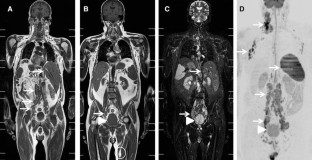

Fig. 1